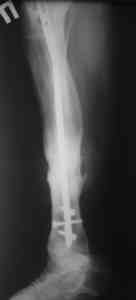

Пример (пациент 46 лет, лечился у нас 4 года назад, внутренний остеосинтез выполнен с определенными погрешностями, но перелом сросся и рецидива инфекции не было): рис. 1,2 - при переводе к нам в институт, рис. 3 - после микрохирругической пластики, рис. 4, 5 - после интрамедуллярного остеосинтеза, рис. 6, 7, 8 - внешний вид и рентгенограммы после окончания лечения

Штифт лучше взять неканюлированный, диаметр 10-11 мм. с большим количеством отверстий для блокирования (лучше ввести все блокирующие винты для создания максимальной стабильности).